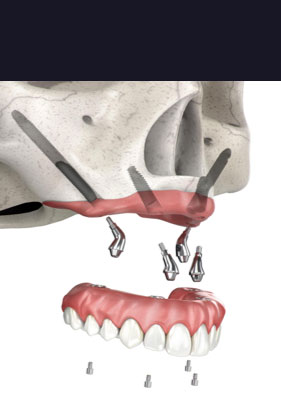

When a patient has insufficient bone structure in the jaw to successfully support a dental implant, a harder bone is necessary in order for the implantation to properly anchor.

Zygomatic dental implants from FastNewSmile® offer a longer dental implant that ranges between 30 and 55 mm. The length of these implants is necessary because we anchor them into a patient’s cheekbone for sufficient stability. Despite deterioration in the jaw, the cheekbone will always hold its strength, making it the ideal location for Zygoma dental implant placement.